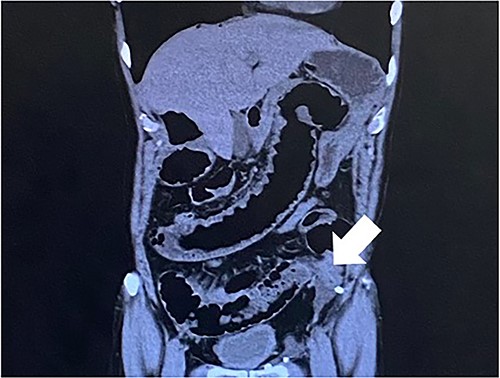

Computed tomography revealed caliber changes in the small bowel at the site of post-hernia repair in the left inguinal region (Figs 1 and 2), and the patient underwent laparoscopic surgery under general anesthesia. Intraperitoneal observation revealed that the peritoneal suture in the left inguinal region was detached, and a hole in the peritoneum had formed a hernial orifice (Fig. 4), causing SBO because of preperitoneal herniation (Fig. 3). The hernia was released, the peritoneal hole was sutured again and the surgery was completed. The postoperative course was good, and the patient was discharged from the hospital on the third postoperative day after reoperation.

The white arrow shows the small bowel incarcerating into the preperitoneal space (coronal section image).

The closed peritoneum was lacerated, and the small bowel was incarcerated in the preperitoneal space.